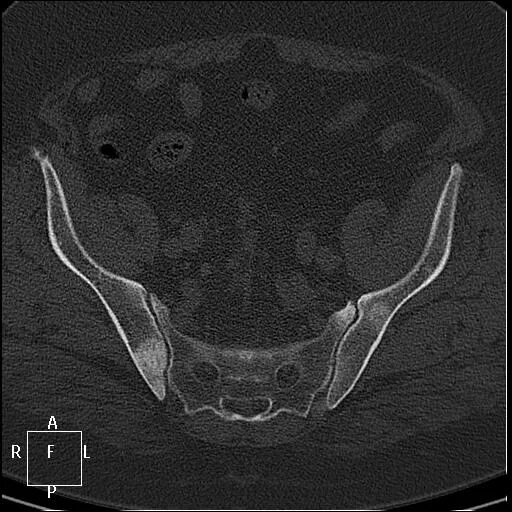

Метастазы в простате